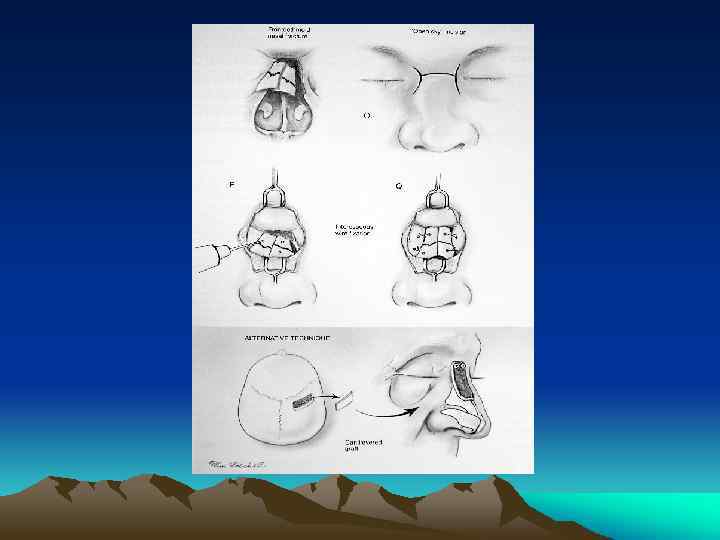

Cont : Management Surgical Management Ø Generally nasal bone depressed or deviation may undergo closed reduction Ø Open Reduction with Internal Fixation (Septorhinoplasty) Ø Pediatric Nasal Fractures: generally should be treated conservatively

Cont : Management Surgical Complications & Associated Injuries Ø Persistent Deformity Ø Nasal Obstruction Ø Septal Hematoma Ø Septal Perforation and Deviations Ø Cribriform Plate Fracture